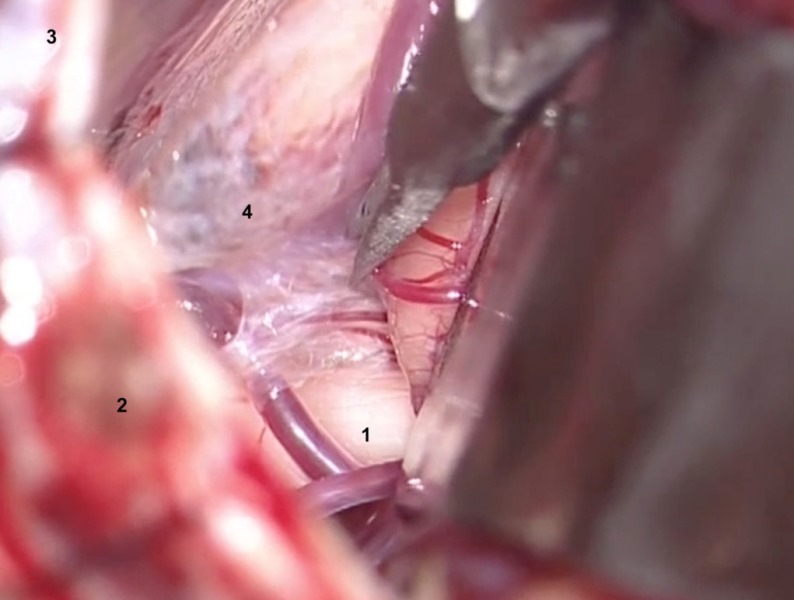

1. The arachnoid overlying the fifth nerve is tightly adherent at the cerebellopontine angle, so it is necessary to perform a sharp dissection, using microscissors ( Figure 6 A). The trigeminal nerve and its relationship to the pons must be fully exposed.

1. Trigeminal nerve.

2. Sigmoid sinus.

3. Transverse sinus.

4. Arachnoid.